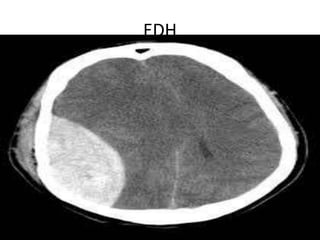

EDH

Trauma • Soft tissueinjuries. • Skull fractures. • Extradural,subdural and subarachniod hemorrhage. • Contusions and diffuse axonal injury with associated cerebral odema.